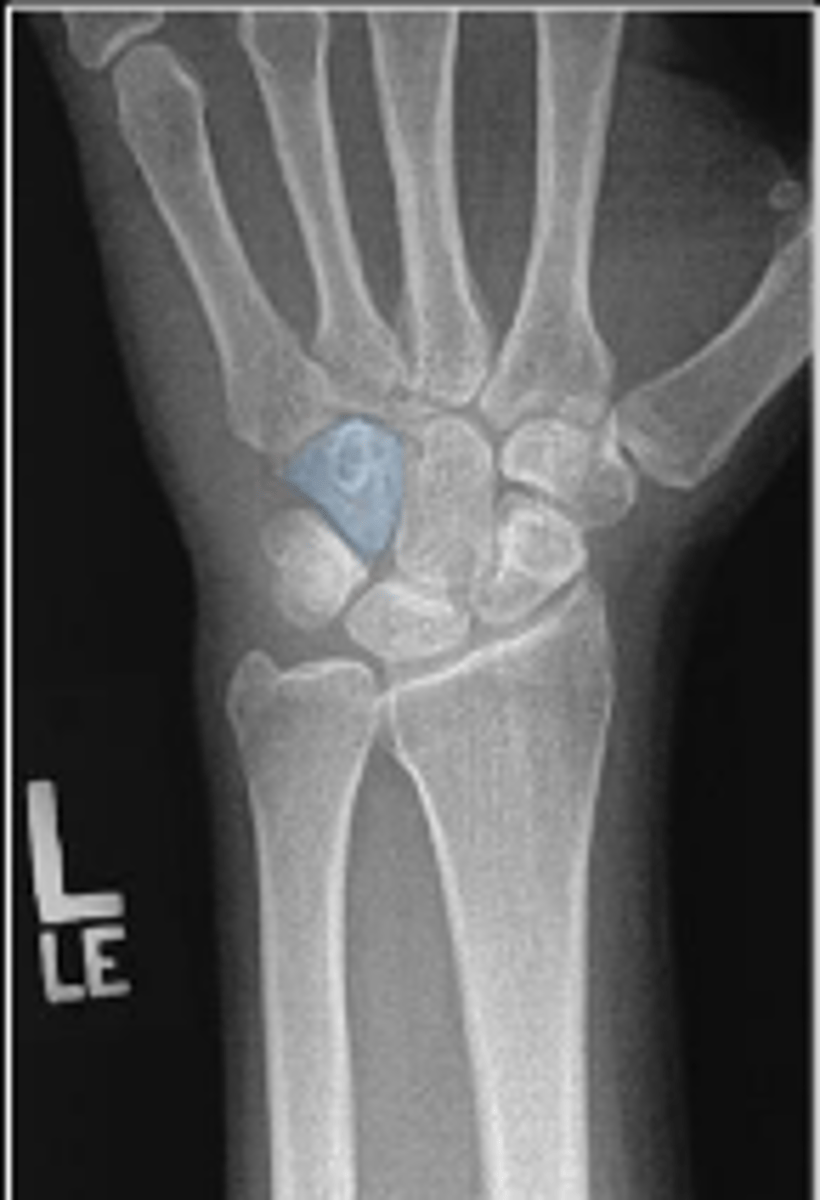

PA of the left wrist

What is the name of the radiographic view?

Left scaphoid

What is outlined?